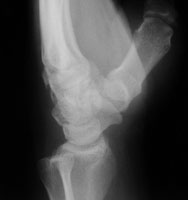

- Click on the image for a larger versionALateral radiograph of the wrist. This shows a bony fragment at the carpometacarpal region.